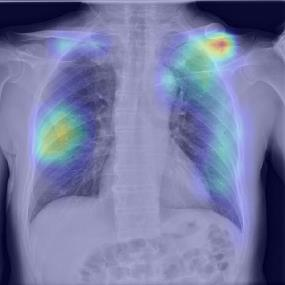

Chest X-ray (CXR) is the most typical diagnostic X-ray examination for screening various thoracic diseases. Automatically localizing lesions from CXR is promising for alleviating radiologists' reading burden. However, CXR datasets are often with massive image-level annotations and scarce lesion-level annotations, and more often, without annotations. Thus far, unifying different supervision granularities to develop thoracic disease detection algorithms has not been comprehensively addressed. In this paper, we present OXnet, the first deep omni-supervised thoracic disease detection network to our best knowledge that uses as much available supervision as possible for CXR diagnosis. We first introduce supervised learning via a one-stage detection model. Then, we inject a global classification head to the detection model and propose dual attention alignment to guide the global gradient to the local detection branch, which enables learning lesion detection from image-level annotations. We also impose intra-class compactness and inter-class separability with global prototype alignment to further enhance the global information learning. Moreover, we leverage a soft focal loss to distill the soft pseudo-labels of unlabeled data generated by a teacher model. Extensive experiments on a large-scale chest X-ray dataset show the proposed OXnet outperforms competitive methods with significant margins. Further, we investigate omni-supervision under various annotation granularities and corroborate OXnet is a promising choice to mitigate the plight of annotation shortage for medical image diagnosis.